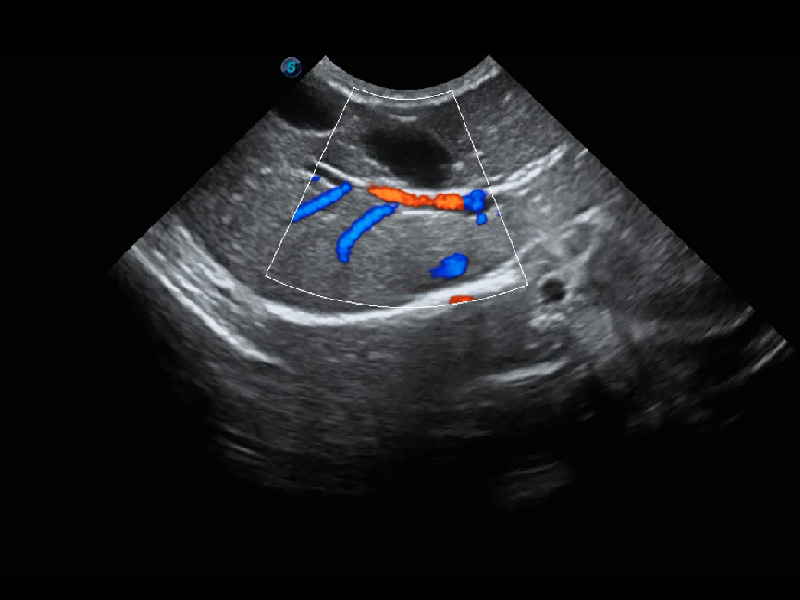

ProPet 60 作为一款高端台式动物超声设备,为动物医生的日常诊断提供了一系列贴合动物临床需求、解决临床实际问题的高级成像功能。凭借全系列高清探头,满足医生对腹部、心脏、生殖、浅表、肌骨等成像的所有需求,切实帮助您提升检查效率,提高诊断信心。

兽用彩色多普勒超声诊断系统

动物是人类最亲密的朋友和最值得信赖的伙伴。竞技宝(JJB)官方网站也一直致力于探索动物专用的超声影像解决方案。 全新推出的ProPet系列,是竞技宝(JJB)官方网站在动物超声影像智能化、专业化、精准化的一次跨越式革新。动物不能用言语来表述自己的不适,通过超声影像,ProPet系列搭建了动物医生与不同物种沟通的“桥梁”,为动物医生注入了“治愈之力”。